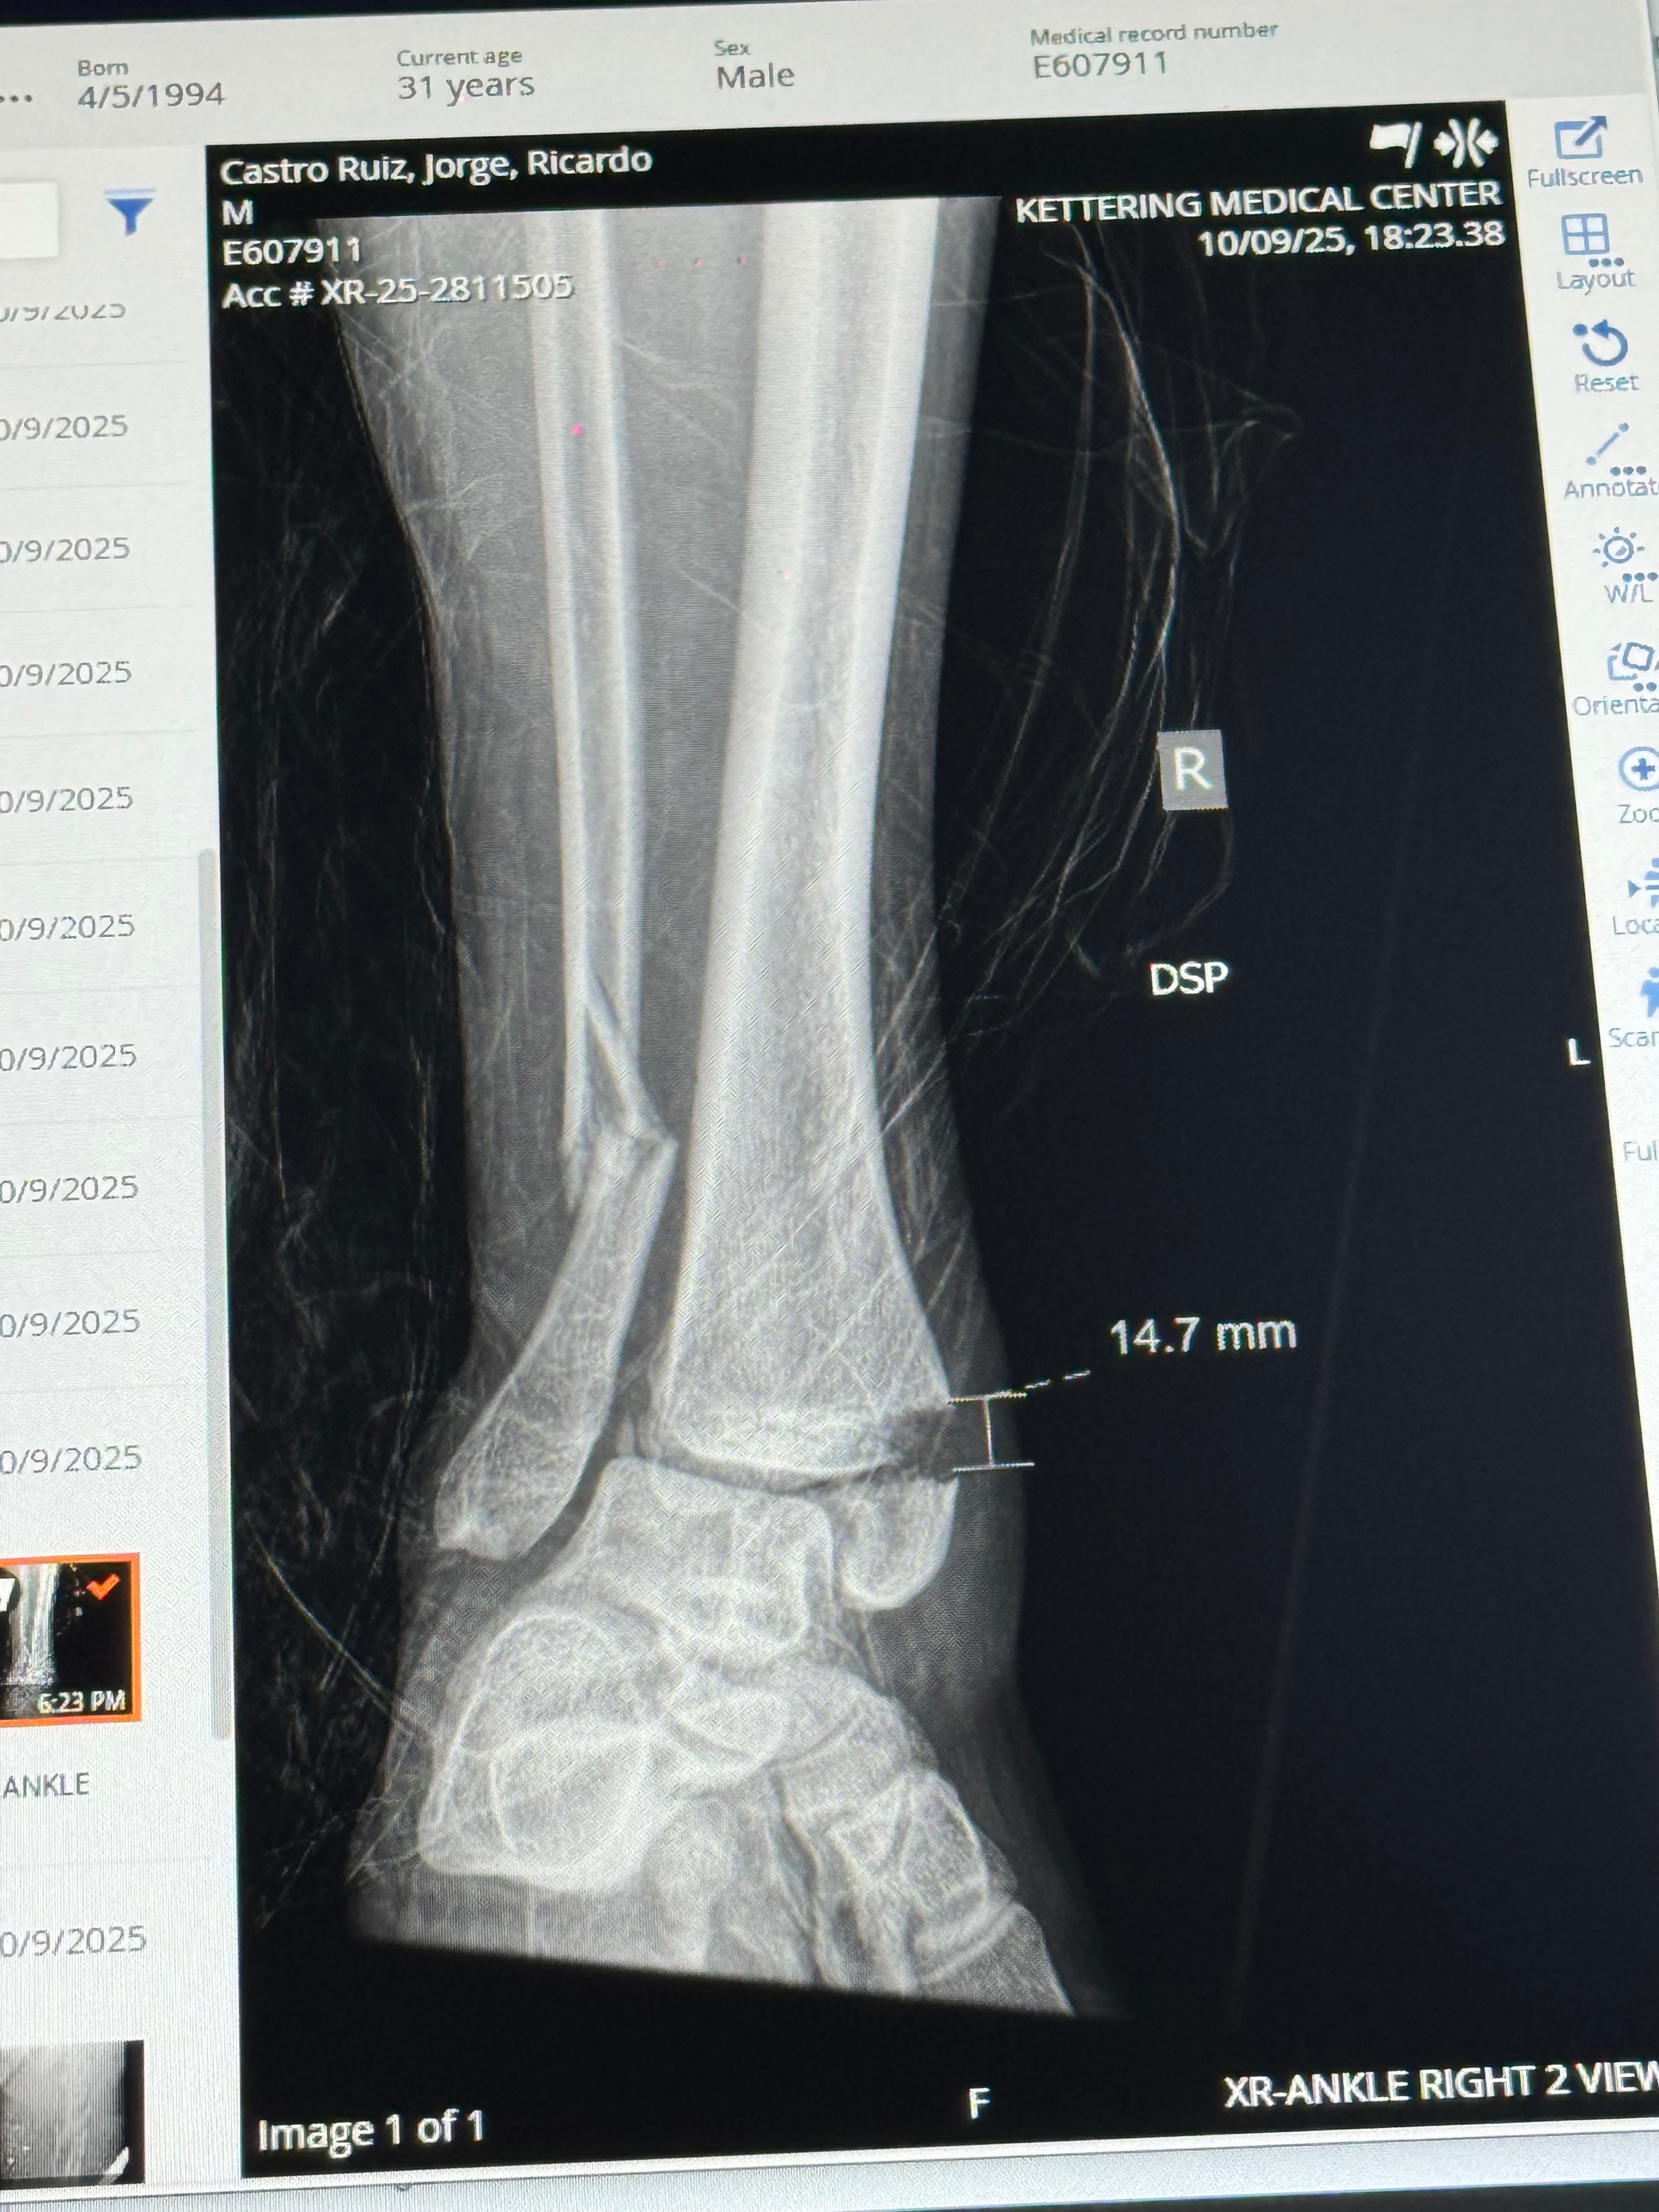

Jorge Castro is a devoted father of two and a talented freelance photographer known for his love of the outdoors and his infectious, bubbly personality. Recently, Jorge’s life changed in an instant when a driver crossed the yellow line on Rahn Rd and hit his car head-on. His four-month-old daughter was in the car with him, but thankfully she was unharmed. Jorge, however, suffered serious injuries, including breaks to both femurs and one ankle. He now faces a long road to recovery and will soon be moved to a rehabilitation facility.